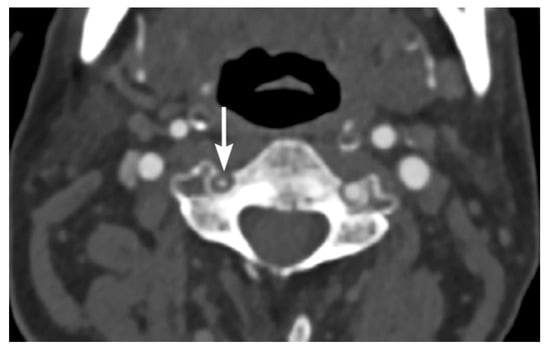

2. Imaging Techniques

3. Imaging Findings of Arterial Injury